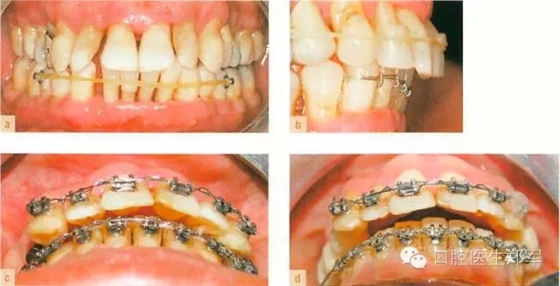

治療選擇:正畸治療(Hawley矯治器)+ 舌面金屬絲加復(fù)合材料的夾板防止復(fù)發(fā)。Hawley矯治器可以分離上、下后牙,前牙的橡皮圈或金屬絲可以使下前牙內(nèi)收,同時使上前牙恢復(fù)到牙列的正常位置(圖6)。

圖6:用橡皮筋和固定托槽來使外展的上下前牙內(nèi)收。依靠復(fù)合材料粘接覆蓋到尖牙上來抬高垂直空間。下頜前牙內(nèi)收后為上頜前牙的內(nèi)收提供空間。